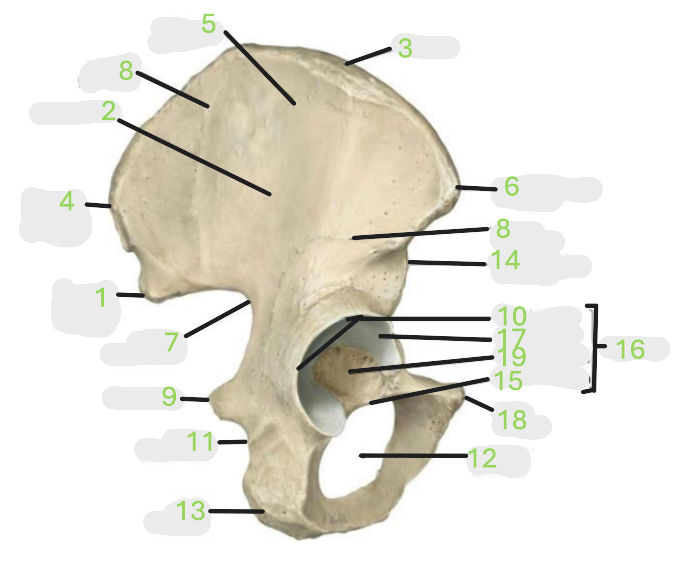

Where is the posterior inferior iliac spine

1

Where is the gluteal surface

2

Where is the iliac crest

3

Where is the posterior superior iliac spine

4

Where is the anterior gluteal line

5

Where is the anterior superior iliac spine

6

Where is the greater sciatic notch

7

Where is the inferior gluteal line

8

Where is the ischial spine

9

Where is the acetabular rim

10

Where is the lesser sciatic notch

11

Where is the obturator foramen

12

Where is the ischial tuberosity

13

Where is the anterior inferior iliac spine

14

Where is the acetabular notch

15

Where is the acetabulum

16

Where is the lunate surface

17

Where is the pubic tubercle

18

Where is the acetabular fossa

19